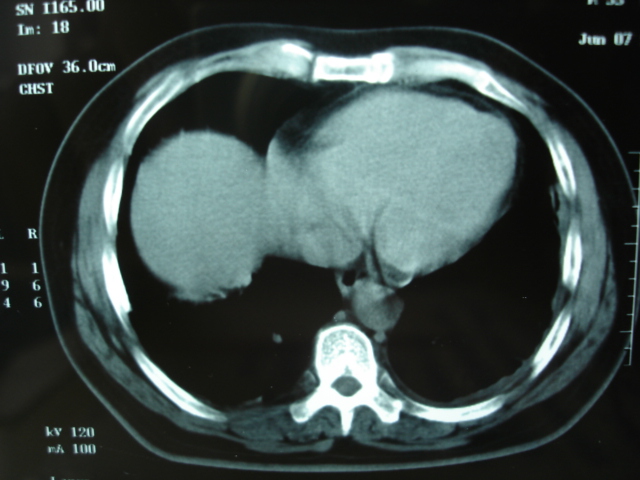

2009.6.4 2009.6.7 2009.8.21

第三次ct2009.8.21

病灶与胸膜成直边征,考虑炎症假瘤可能性大。

考虑左肺上叶炎症感染(炎性假瘤可能)。

考虑 左肺上叶炎症感染 [炎性假瘤可能性大]。

考虑左肺上叶炎症感染,以炎性假瘤可能性大。